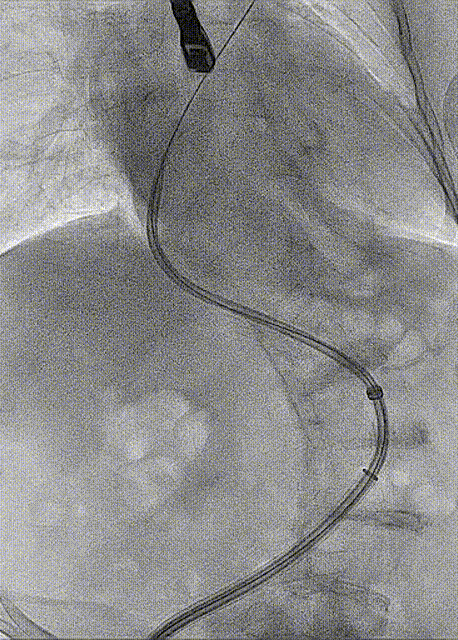

房间隔穿刺

手术过程